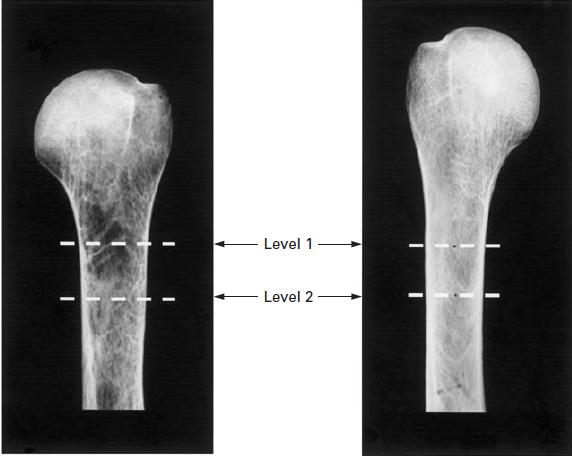

2.Tingart Index 4.4mm。肱骨近端骨皮质的厚度大于4.4mm,骨质情况良好做内固定,小于4.4mm骨质疏松做关节置换。

L1:内外侧皮质相互平行最高点 L2:L1远端2cm处Tingart Index= L1+L2的皮质厚度